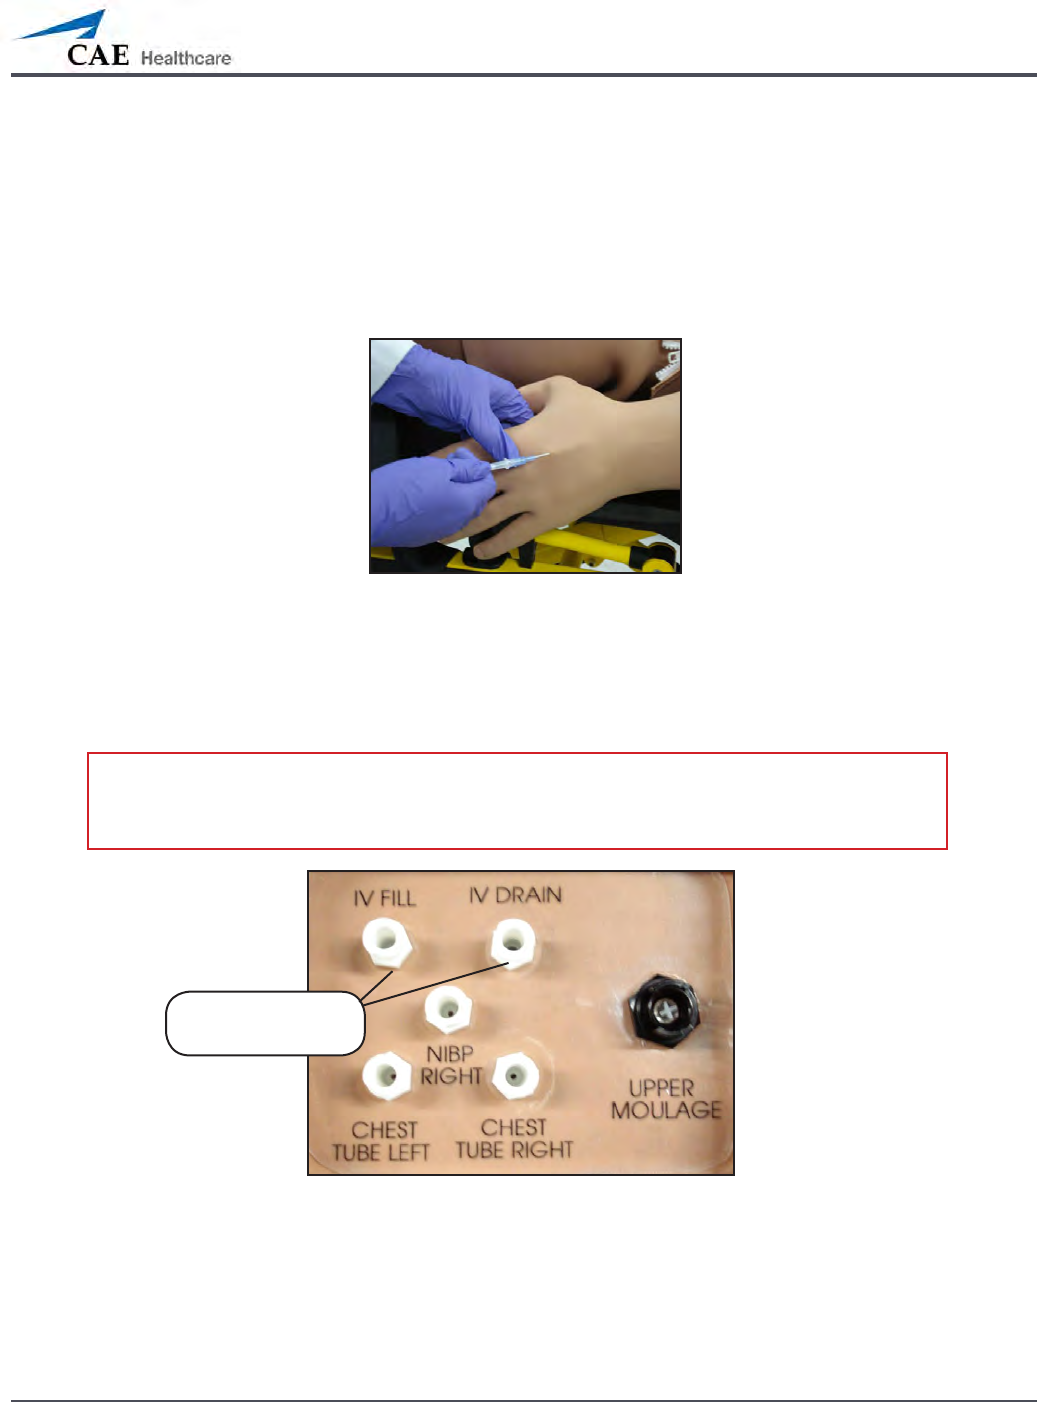

IV Cannulation

Veins for the IV Cannulation feature are located in the dorsum of the hands, forearms and

antecubital region of the arms. Use only a 20- to 22-gauge needle. To simulate realistic

ashback, the system must be primed prior to use. Ensure all uids have been removed

from previous uses before each new use to prevent overlling. Please refer to the Care and

Maintenance section for directions on uid removal.

IV Cannulation

To prime the IV access ports, connect a 60 mL syringe lled with distilled water (with clinically

appropriate food coloring if desired) to the IV FILL port on METIman’s right shoulder and rmly

inject all 60 mL. This primes the arms and charges the system for Flashback and Venipuncture

support.

METIman’s Right Shoulder

Fluids and medications can be administered intravenously. Approximately 50 mL of uid may

be infused. To support infusion of larger volumes, connect an empty IV bag or other receptacle

to the IV DRAIN port located on METIman right shoulder.

IV FILL and IV

DRAIN ports